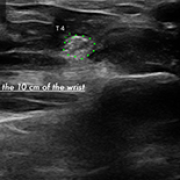

Evaluation of Splint and Exercise Interventions for Carpal Tunnel Syndrome: Insights from Ultrasonographic Measurements

DOI: 10.12659/MSM.945704

Med Sci Monit 2024; 30:e945704

02 Nov 2024 : Clinical Research

Sibel Çağlar

, Tuba Altun

, Meltem Vural

, Murat Mert

5,991